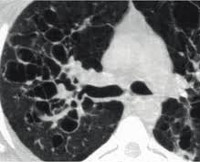

• Радиационная диагностика. Грубое усиление и деформация легочной модели, буллезная эмфизема выявлены при обзорной рентгенографии ОГК. КТ легких показывает общий бронхоэктаз. При кинематографической бронхографии их расширение и спад (воздушный шар) можно наблюдать во время акта дыхания.